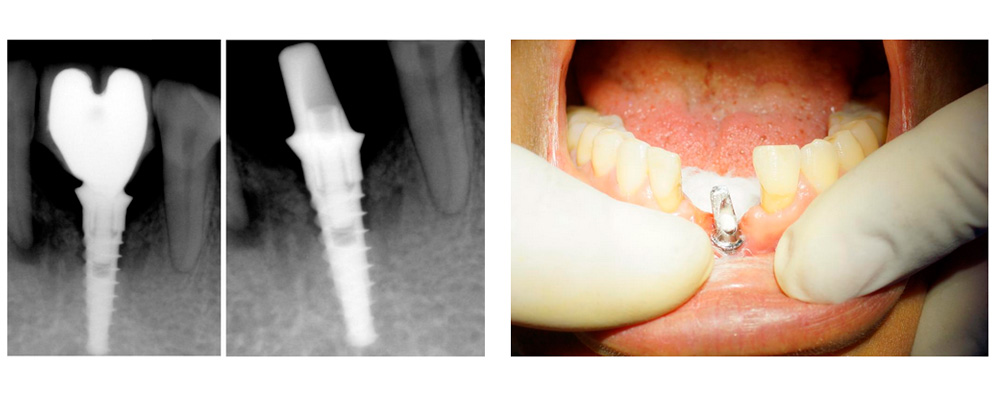

Tratamiento: La falta de espacio interproximal y la ausencia de hueso del reborde alveolar nos obliga a la colocación de un solo implante dental de titanio DSI con conexión interna hexagonal (3.75 de diámetro y 13.0 mm de longitud) sobre la línea media en la zona mentoniana, como lo muestra la radiografía periapical de la figura 3 y la clínica en la figura 4; la medición del OSSTELL aloja 58 ISQ a los 4 meses de la colocación del implante (fig. 5). Para la rehabilitación protésica se usa un pilar angulado a 17 grados como se muestra en la figura 6 y 7; en la radiografía de la figura 8 se muestra una corona de metal porcelana y dos pónticos para sustituir los centrales inferiores y la caracterización de la encía en porcelana (fig. 9).